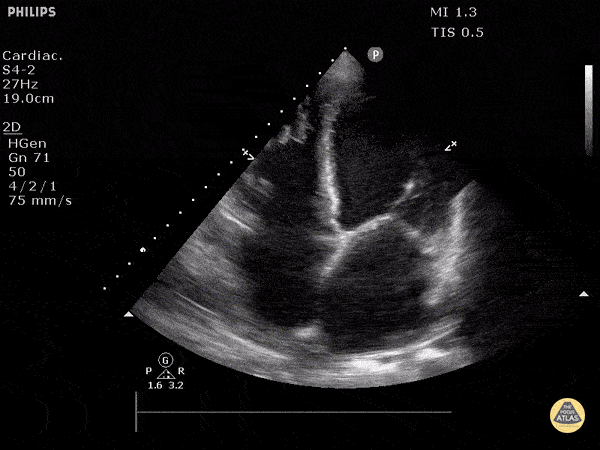

https://www.thepocusatlas.com/left-ventricular-dysfunction

View: Unspecified Parasternal Long Axis Parasternal Short Axis Apical Four-Chamber Subcostal Four-Chamber Subcostal Inferior Vena Cava Right Upper Quadrant Left Upper Quadrant Suprapubic Longitudinal Suprapubic Transverse Subxiphoid Anterior Thoracic Phrenic